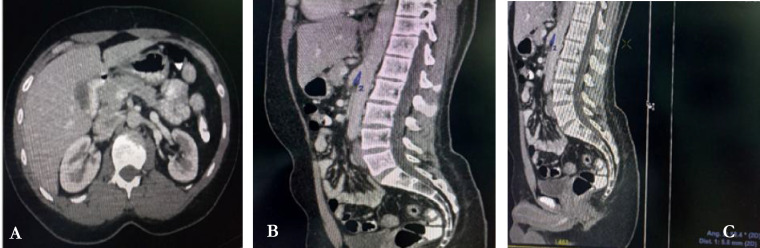

Case presentation: This is a case series report of two patients that presented at the emergency unit with acute exacerbation of insidious onset of upper abdominal pain. Radiological evaluation with computerized tomography proved the presence of this pathology in both patients with reduction in aortomesenteric angles and distances. The management of this clinical entity is largely conservative with surgical intervention rarely needed.